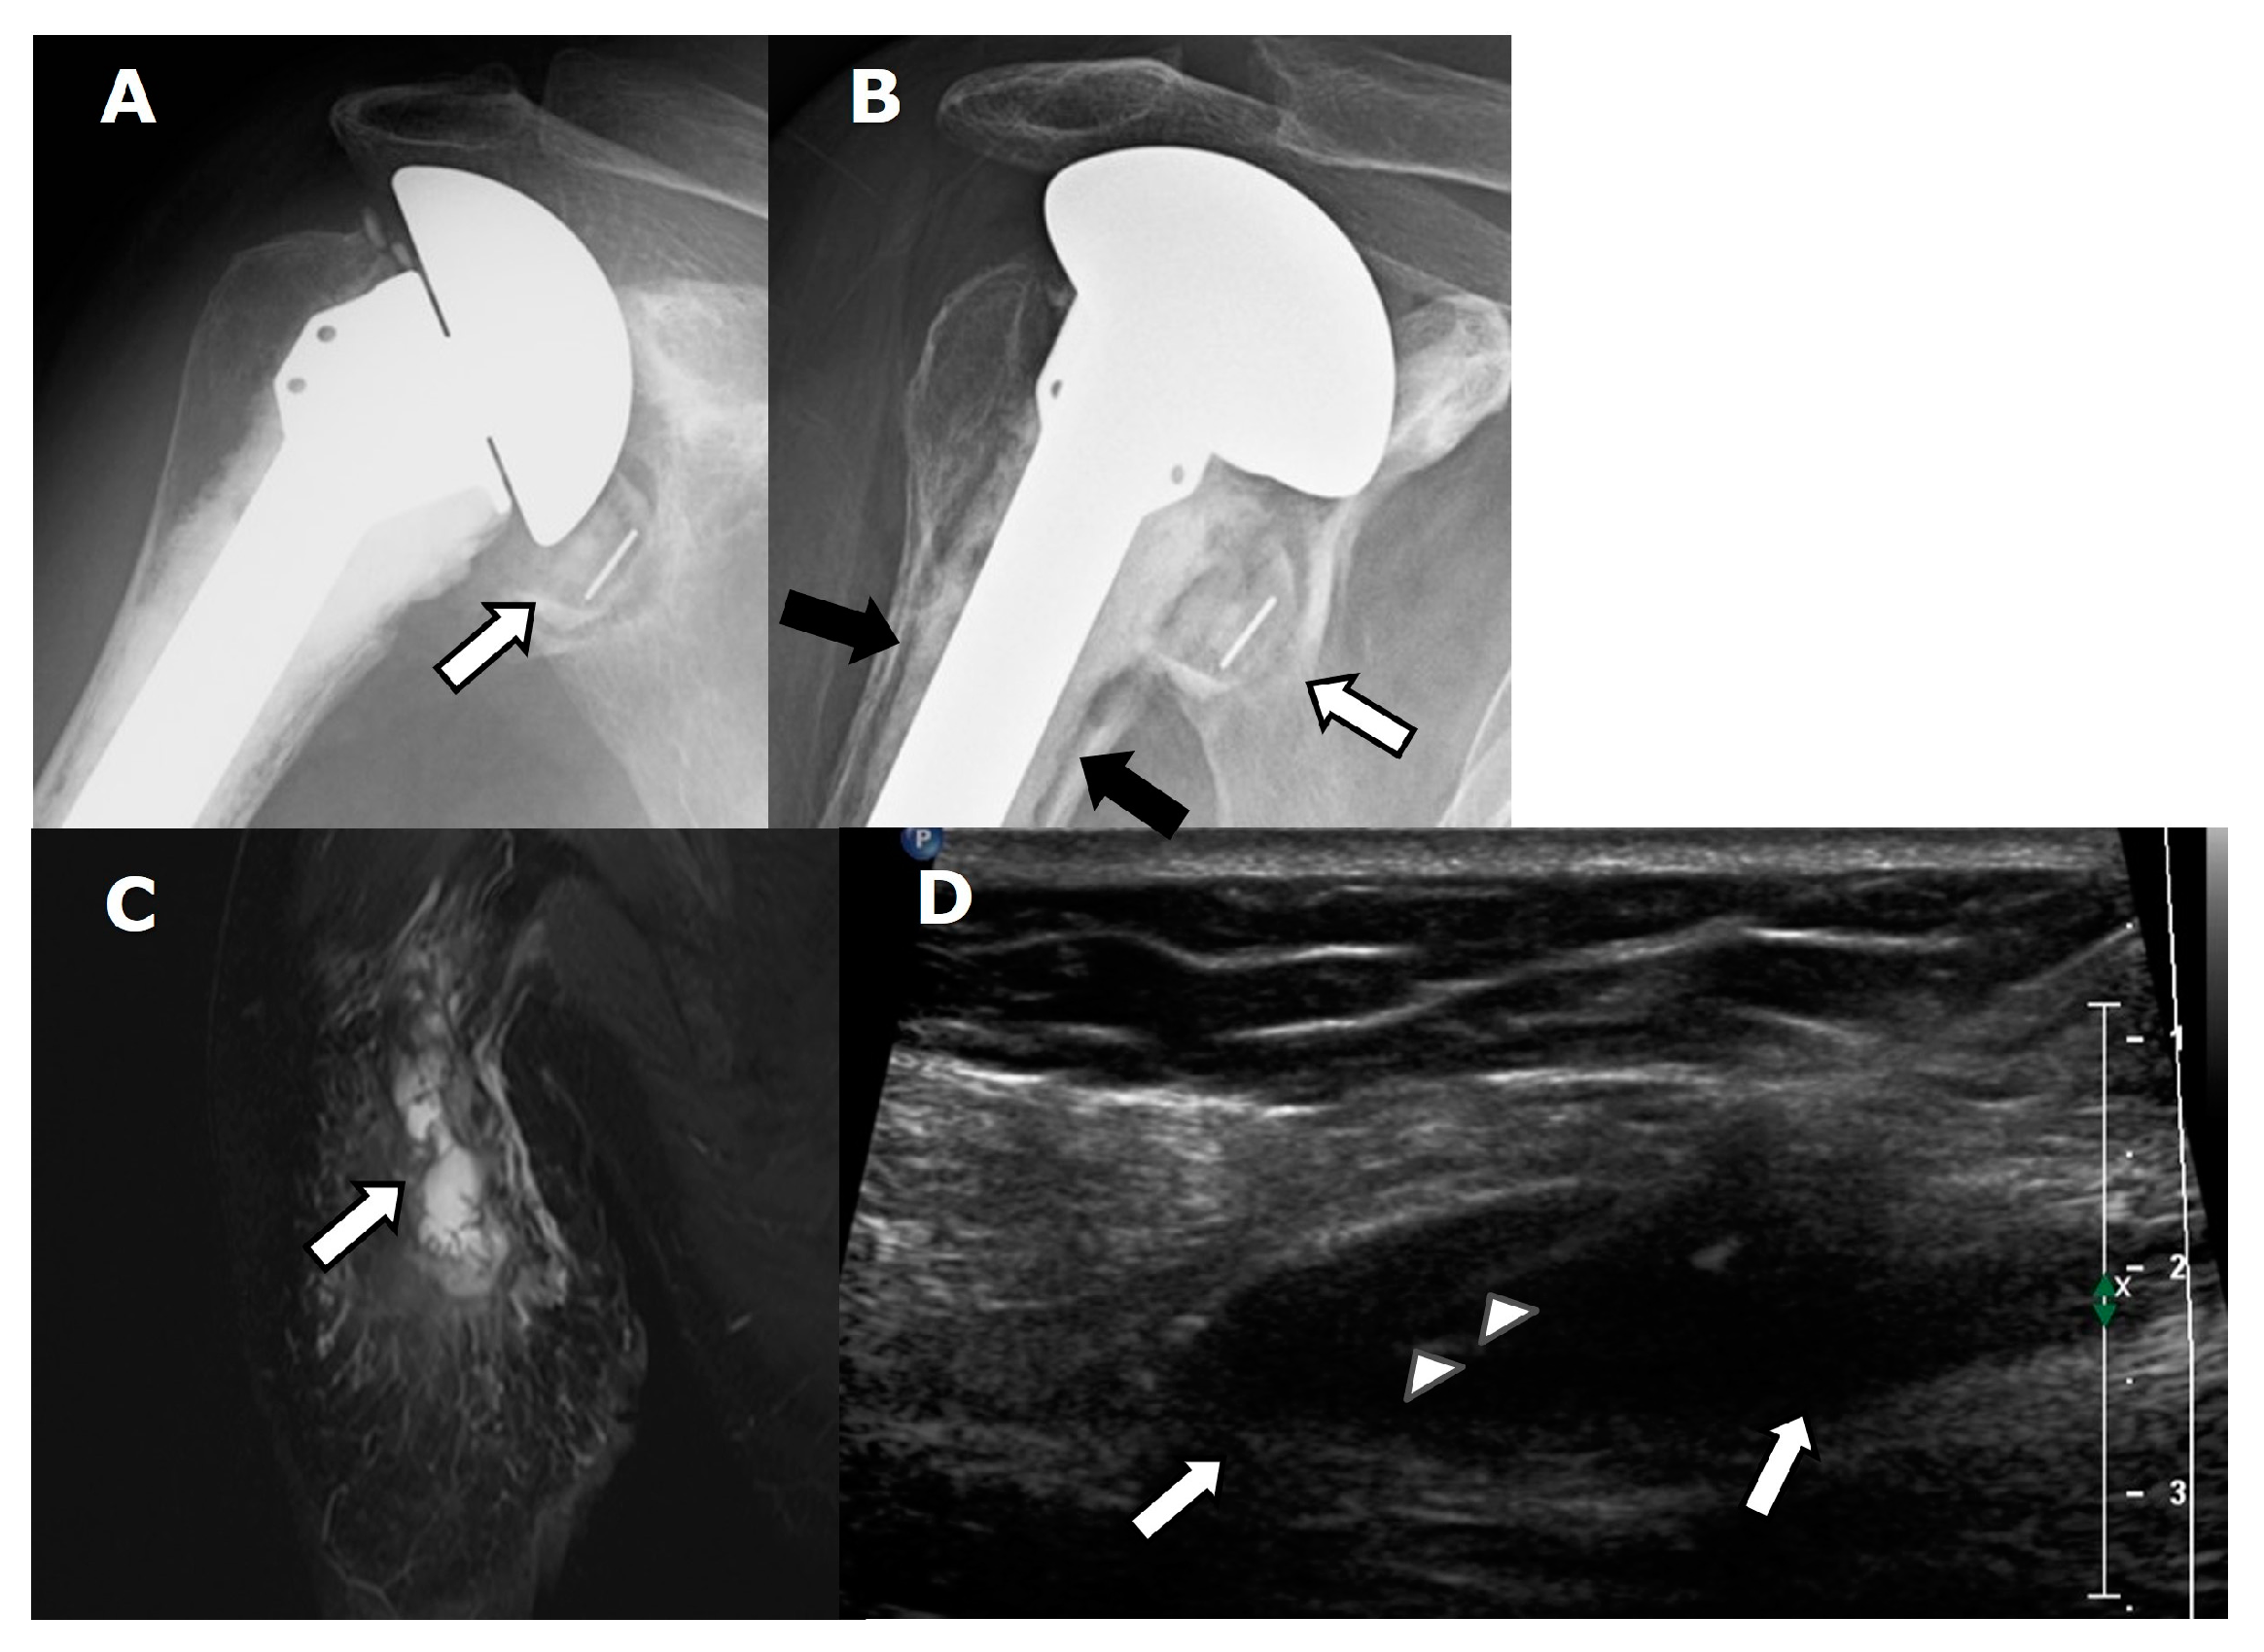

4.2. General Complications

4.2.1. Loosening and Hardware Dissociation

4.2.2. Stress Shielding and Fractures

4.2.3. Periprosthetic Joint Infection (PJI)

4.2.4. Rotator Cuff Tendon Tears